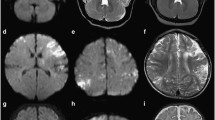

Neuroimaging features

Among the five neonates with COVID-19, four neonates presented with WM changes, including two full-term neonates (neonate 1 and neonate 3) who had hypoxic changes. As shown in Supplementary Fig. 2, there are signal changes of varying intensity in the basal ganglia region in T1WI. One neonate (neonate 4) and one full-term neonate (neonate 5) had brain hypoplasia with delayed myelination. MRI of the other neonates with COVID-19 revealed no significant abnormalities.

Four of the five infected neonates had abnormalities in cranial MRI. The fourth case was a 31-week gestational age premature infant, and two of the remaining three cases had hypoxic changes; the fifth case had abnormal signals in the bilateral ventricular WM region. The four neonates with abnormal MR signals did not show any obvious signs of hypoxia or asphyxia after birth. It should be further explored whether the hypoxic changes shown in MRI are already present in utero.